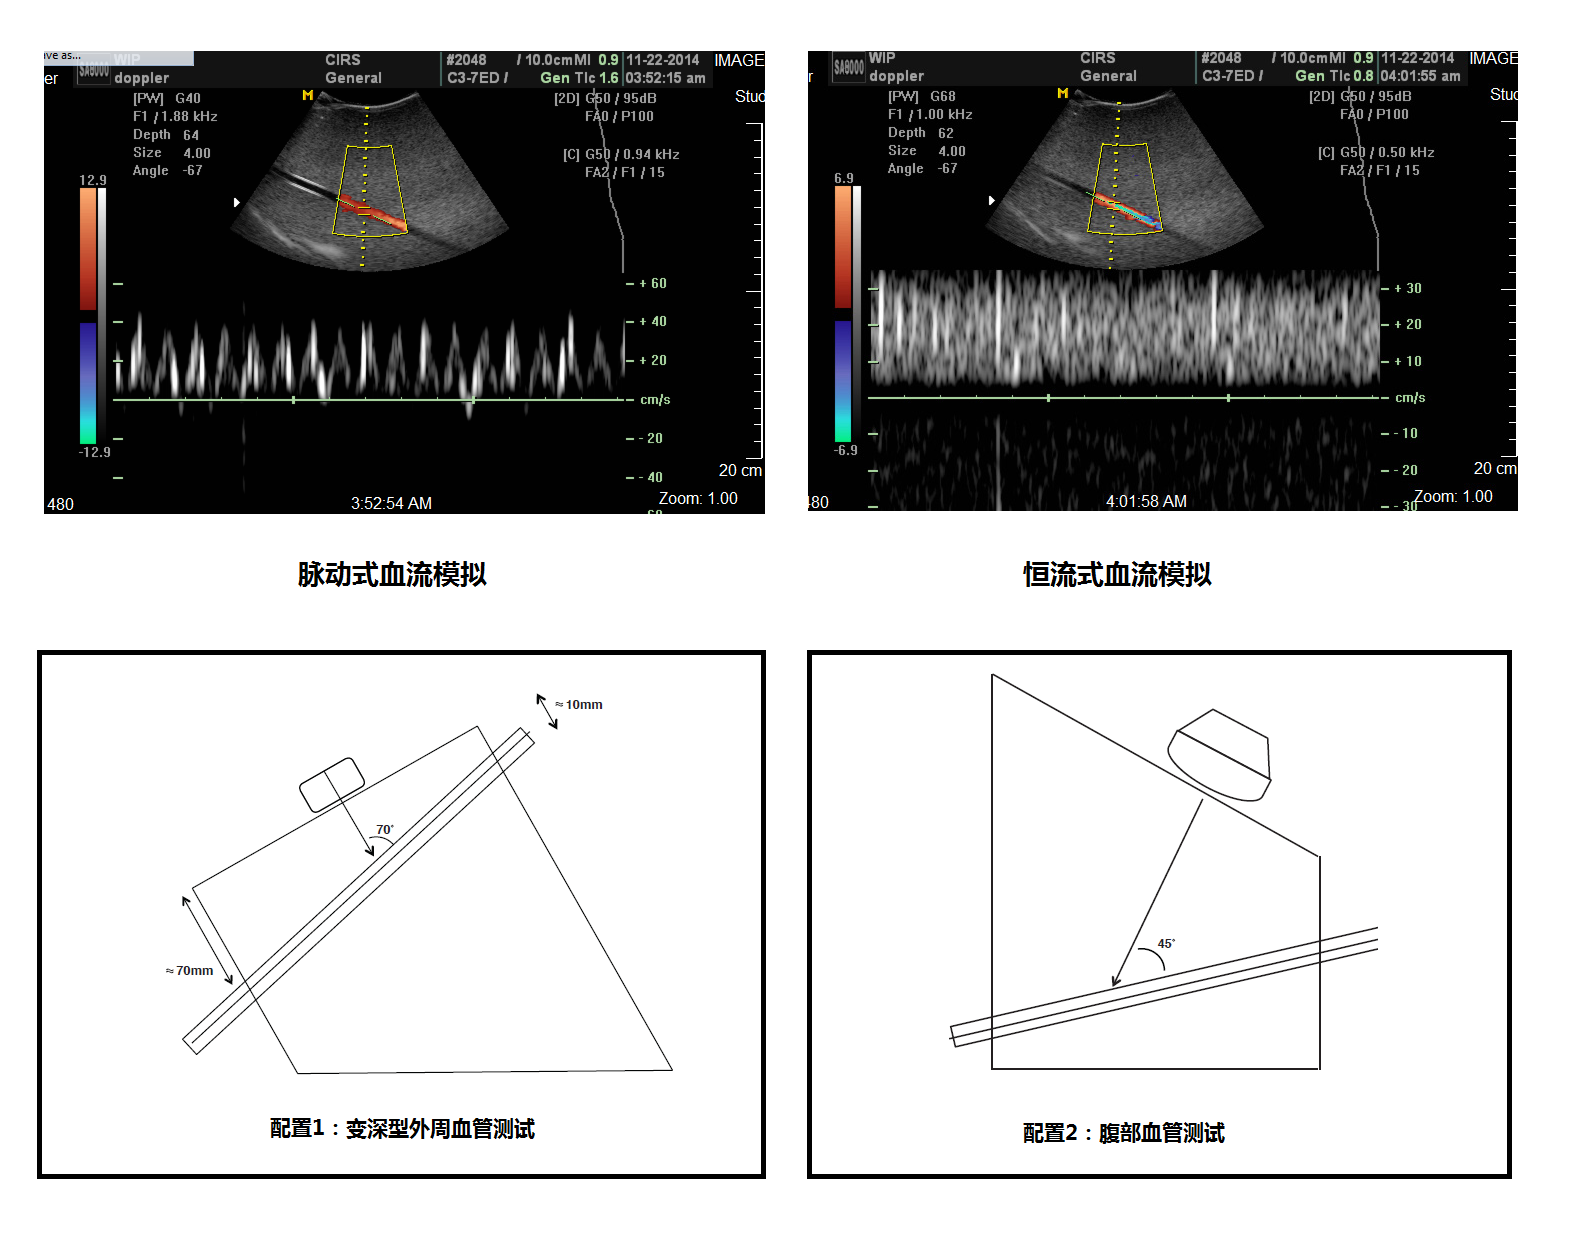

超聲多普勒流量模擬機(jī)是專門為了在仿真組織內(nèi)模擬血流量的模體,可以使用在測量超聲多普勒儀器的質(zhì)量檢測應(yīng)用之中。常用的兩個測試為靈敏度和速度準(zhǔn)確性,除此之外還可以應(yīng)用在其他幾個測試,詳情請察看相關(guān)附件。

模擬機(jī)包含一個仿真流量模體,一條模擬血管的超聲配用導(dǎo)管斜插在模體之中。模體頂部和底部均設(shè)有掃描表面,提供不同深度和角度的應(yīng)用需要。這樣的設(shè)計(jì)充分發(fā)揮模體的靈活性來測試皮表掃描和深度腹腔血管的掃描的需求。

•脈沖流和均速流兩種選擇

•漸變深度,表層和腹腔血管模擬

模塊1 內(nèi)置血管1條,夾角45°70°,血管內(nèi)徑3/16in,模擬腹部血管,外周血管

模塊2 內(nèi)置血管4條,血管夾角18° 56°,血管內(nèi)徑2/4/6/8mm,模擬腹部血管,心臟血管